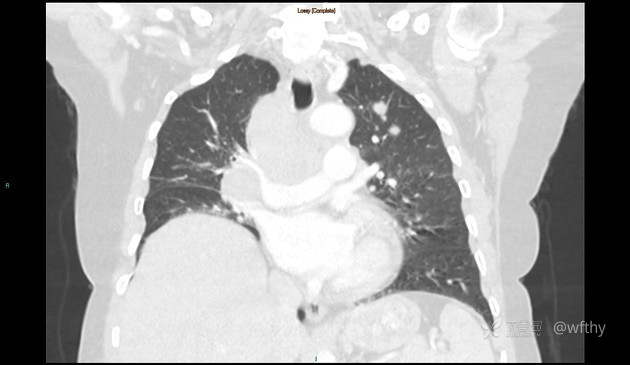

病例女65,头部肿块